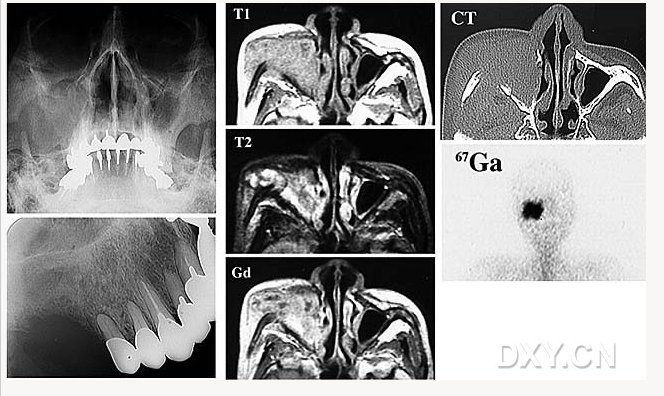

舍格倫綜合征

鼻腭囊腫